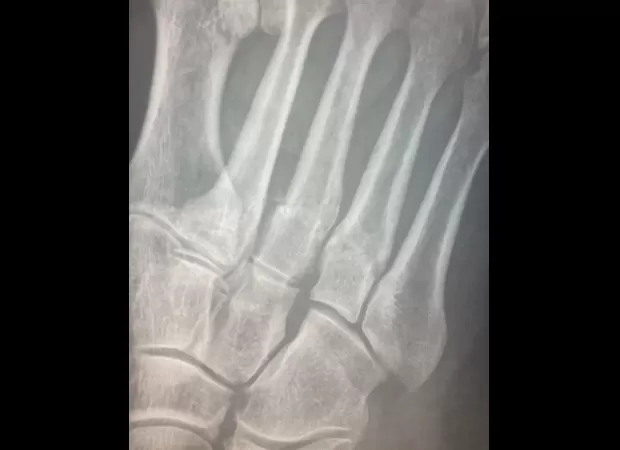

Denise shared images of her injury and the recovery process on her social media and expressed her gratitude for the NHS doctors and nurses. She wrote: ‘Now I’m mending I can tell you. I broke my wonky arm.

As I fell I dropped what I was carrying which broke my foot. Know Hoffnung’s Bricklayers joke? Google it.